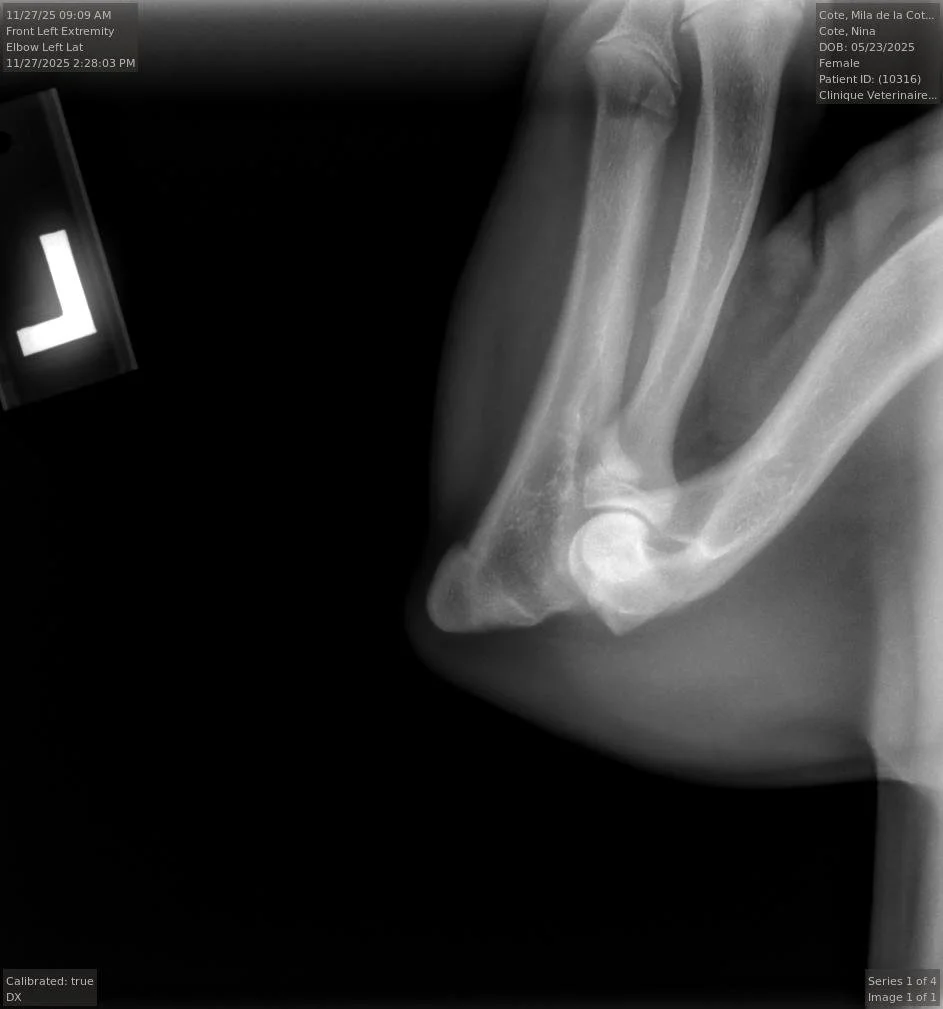

Nous commencerons les tests OFA de la race dès l'âge de 6 mois.